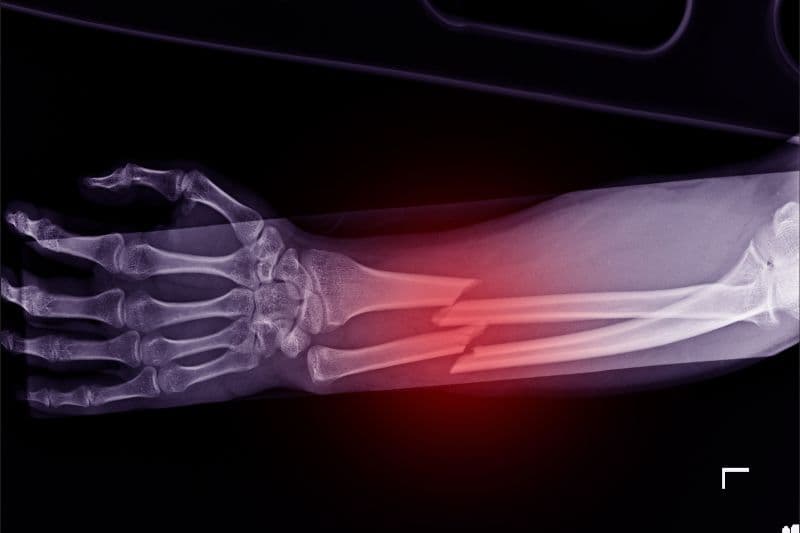

1.3. Gãy xương cổ tay

Gãy xương cổ tay thường xảy ra khi người bệnh chống tay xuống đất trong lúc bị ngã. Đây là loại gãy xương thường gặp ở phụ nữ lớn tuổi có mật độ xương thấp.

Một số triệu chứng điển hình gồm: đau và sưng vùng cổ tay, biến dạng cổ tay, hạn chế vận động bàn tay.

Dù không nguy hiểm như gãy xương hông, nhưng nếu không điều trị đúng cách, gãy cổ tay có thể làm giảm chức năng vận động lâu dài.